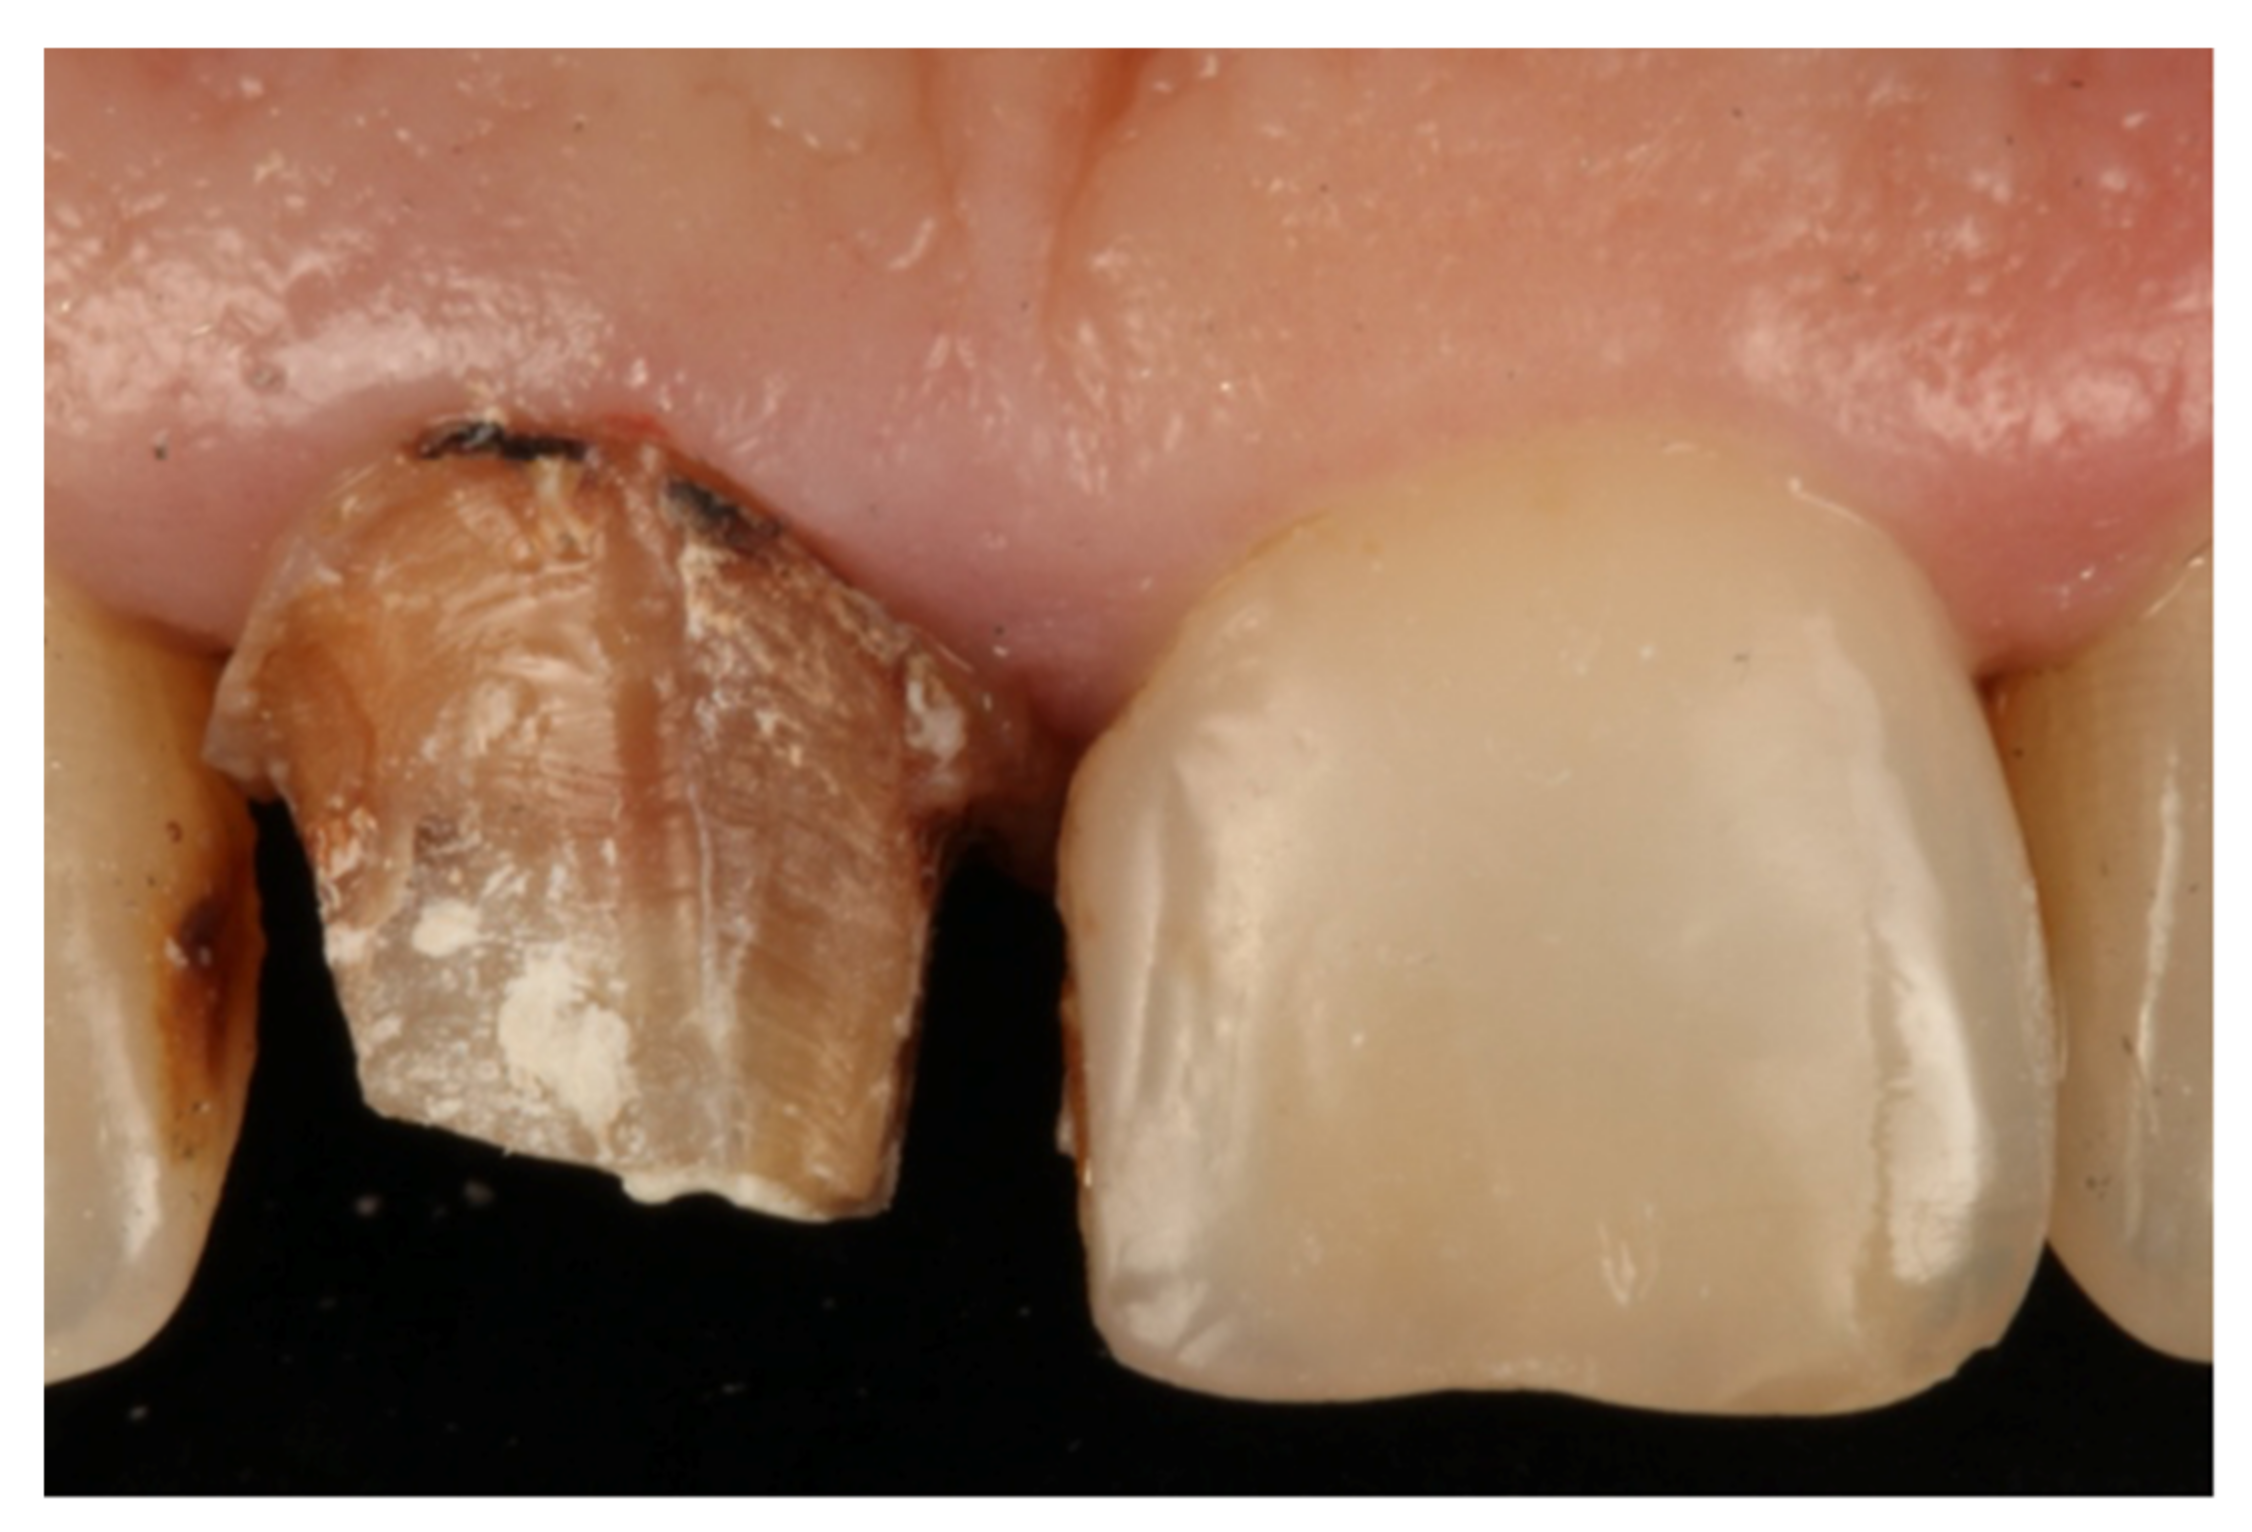

- Teeth treated with this technique presented improved plaque indices, stable probing depths, increased gingival thickness, and stable gingival margins over the 6-year follow-up.

- Treatment with a fixed prosthesis using the BOPT technique has a positive impact on patient satisfaction, especially in cases concerning the re-treatment of old fixed prostheses. This fact is due to the esthetic improvement not only of the restoration but also of the surrounding tissues, as it improves gingival quality by thickening the tissue, thus preventing gingival recession.